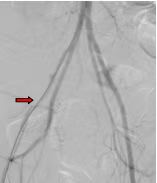

患者,女,50岁,主因腹膜后恶性肿瘤术后出现引流管出血逐渐增加,转入我科行介入治疗,造影提示:右侧髂外动脉中段造影剂外渗、局部大片造影剂滞留,考虑髂外动脉破裂出血,行4*40mm球囊以6atm压迫止血后造影出血明显减少,遂行髂外动脉覆膜支架植入术彻底解决患者出血问题,为患者后续治疗。

术前造影 球囊压迫止血后造影 支架植入术后